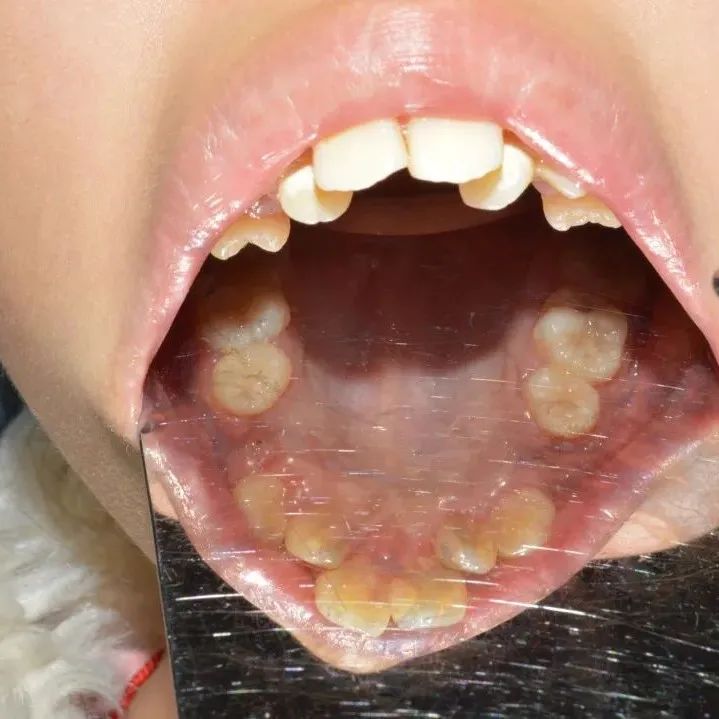

患者女:吴*怡  年龄:17岁主诉:右上后牙破损现病史:右上后曾在我院做了根管治疗既往史:体健,无高血压,心脏病,糖尿病等检查:右上6裂开,腭侧牙冠脱落,探龈下3mm,根尖无明显炎症,牙龈无红肿、瘘管,CT显示髓室底穿孔。右上8牙周状态良好,牙冠完整,根尖无炎症,牙根未发育完成,符合做移植术。和患者家属沟通后同意做移植术,右上8移植到6.患者拍CT后3D打印右上8测量牙冠大小合适。右上8拔除,未拍照6拔牙窝情况。...